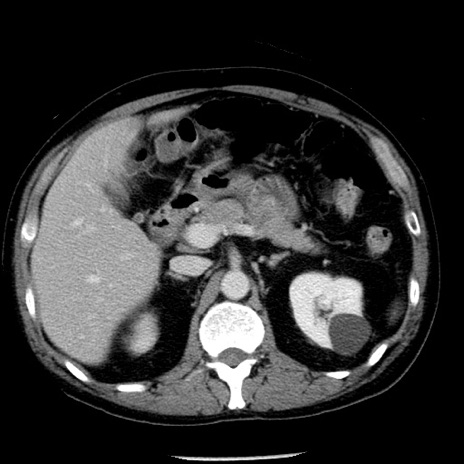

症例29(横断像)

【症例】40歳代男性

【現病歴】2日前から胃痛あり。徐々に周期的な激痛に変化した。本日になっても激痛があるため受診。

【身体所見】意識清明、BT 38-39℃台あり、腹部:膨満、やや硬、右下腹部に圧痛あり。

【データ】WBC 8500、CRP 23.26